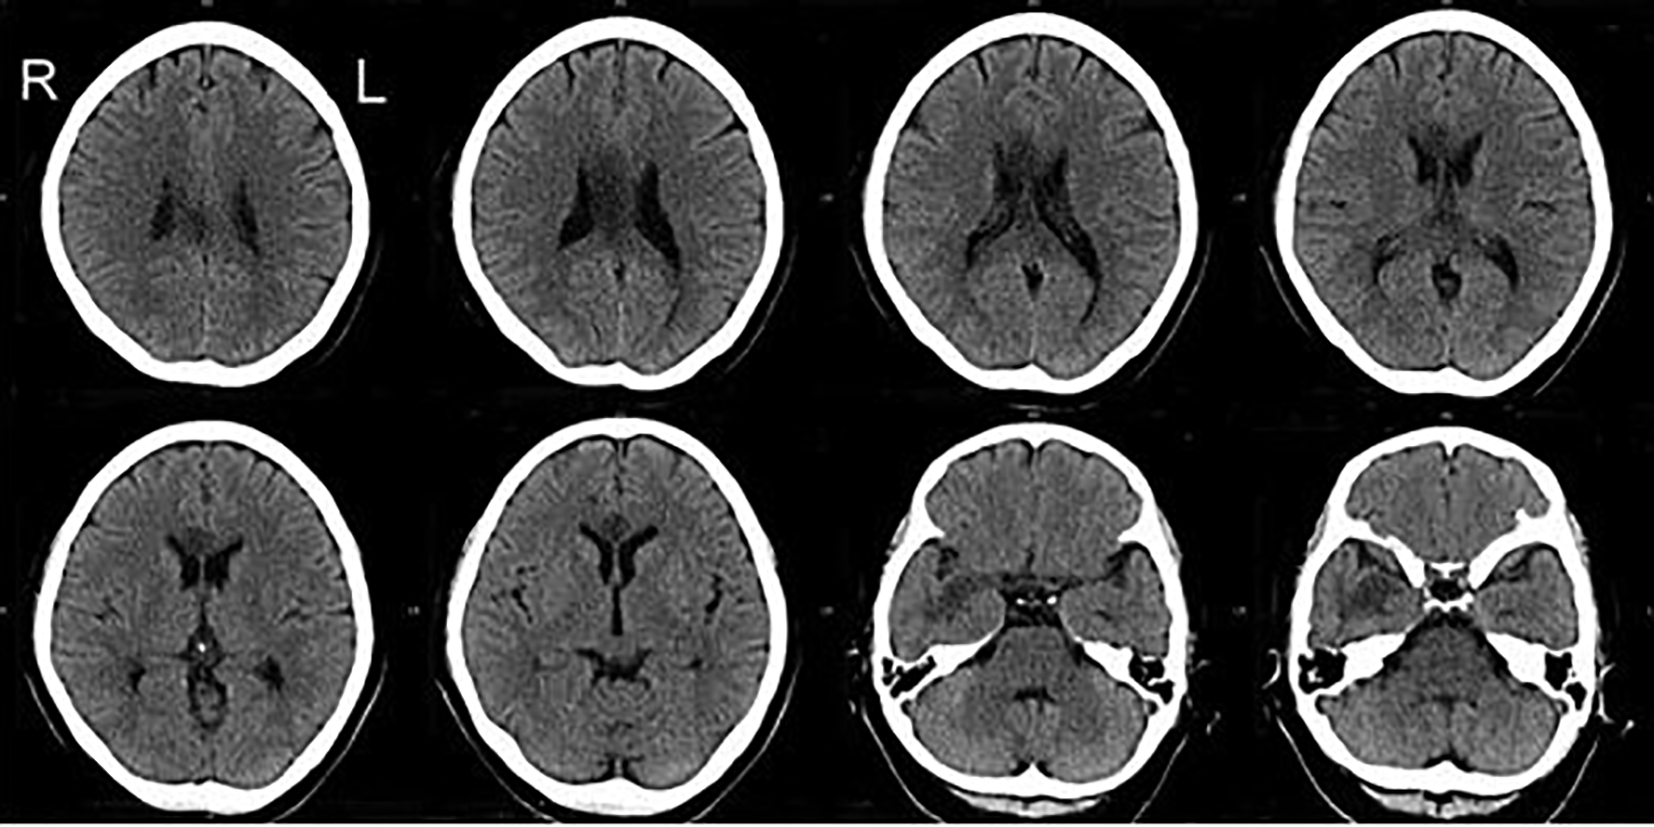

A 57-year-old, right-handed female with risk factors of type II diabetes mellitus and hypertension presented with a sudden onset of left-sided body weakness and slurred speech. The Glasgow Coma Scale (GCS) was 15/15, and her blood pressures were normal. The medical research council (MRC) motor power scale indicated a 4/5 strength in her left upper and lower extremities. Computed tomography (CT) scan of the brain revealed an acute right temporal infarct. The following day, her GCS dropped to 10/15, accompanied by elevated blood pressure. A repeat CT scan displayed an evolution of the right temporal infarct and a new acute corpus callosum infarct extending from the right genu to the left side of the splenium (Figure 1 and Figure 2). Subsequent CT angiography (CTA) revealed short segment stenosis of the proximal M1 segment of the right middle cerebral artery (MCA), left fetal PCA, and hypoplastic right posterior communicating (PCOM) artery. Three weeks post-stroke, she was transferred to the rehabilitation unit.

The CT images demonstrate hypodensity over the corpus callosum extending from the right genu to the left side of the splenium and the right temporal lobe. CT, computed tomography.